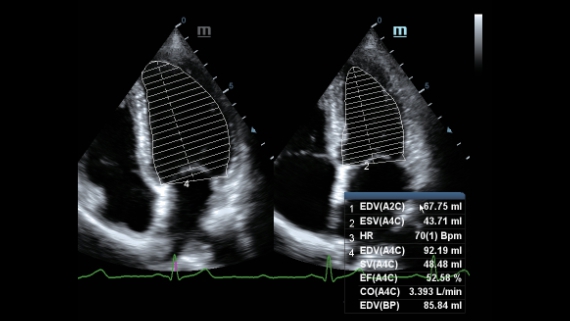

AtenciĂłn dedicada para ECO

Como colaborador versĂĄtil, DC-60?ECHO con X-Insight tiene por objetivo proporcionar una soluciĂłn integral para ayudarlo a administrar todos los aspectos de la prĂĄctica clĂnica diaria con facilidad y seguridad.

Sobre la base de un profundo conocimiento de las necesidades del cliente, el DC-60?ECHO con X-Insight estå dise?ado para brindar alta eficiencia con imågenes precisas, lo que se ve potenciado con eXpress Clarity (claridad exprés), eXceptional Intelligence (inteligencia excepcional) y eXceeding Experience (experiencia extraordinaria).

eXceeding Experience

Experiencia con alta productividad